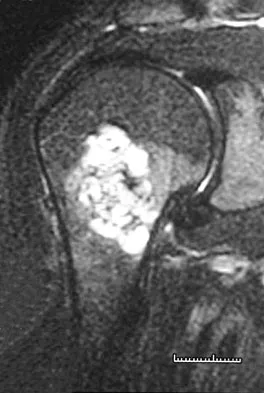

A 45-year-old man reports right shoulder pain with overhead activities only. Figures 47a through 47d show the radiographs, bone scan, and MRI scan of a lesion of the proximal shoulder. What is the most appropriate treatment?

The figures show a lesion of the proximal humerus consistent with an enchondroma. The lesion is calcified on the radiographs. There is no cortical destruction, significant endosteal scalloping, or soft-tissue mass. The bone scan shows mild uptake in the area of the proximal humerus, and the T2-weighted MRI scan shows a lesion with high uptake, suggesting a lesion with high water content. A CT scan could also be obtained to rule out bone destruction or periosteal reaction. Pain with overhead activities is likely related to the rotator cuff. A biopsy is unlikely to add information because of inherent difficulties interpreting low-grade cartilaginous lesions. Curettage and grafting and en bloc resection are excessive treatments for a benign lesion that is apparently asymptomatic. Observation with a follow-up radiograph in 3 to 6 months is appropriate. Menendez LR (ed): Orthopaedic Knowledge Update: Musculoskeletal Tumors. Rosemont, IL, American Academy of Orthopaedic Surgeons, 2002, pp 103-111.